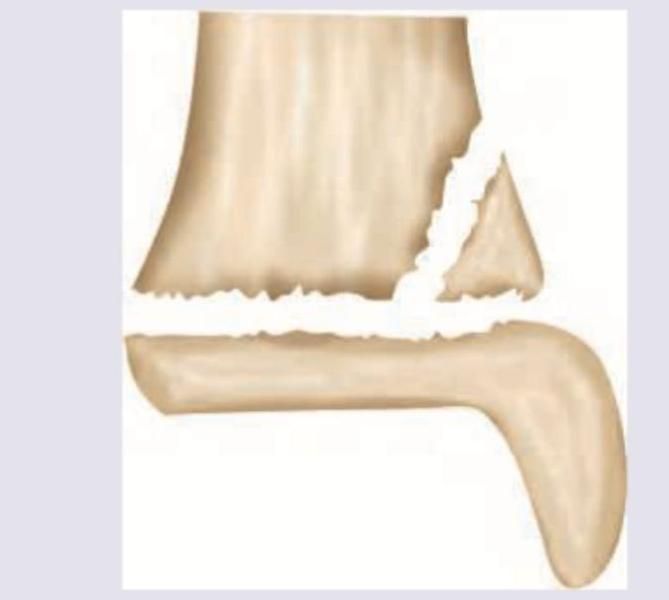

Explanation: ***Greenstick fracture*** - The X-ray image shows an **incomplete fracture** where one side of the bone is broken and the other side is bent, which is characteristic of a greenstick fracture. - This type of fracture is common in children because their bones are **more flexible** and less brittle than adult bones. *Nonunion* - **Nonunion** refers to the failure of a fractured bone to heal after a sufficient period, typically presenting with persistent pain and mobility at the fracture site long after the injury. - This image shows an **acute fracture** with no signs of attempted or failed healing. *Malunion* - **Malunion** occurs when a fractured bone heals in an anatomically incorrect or deformed position. - The image depicts an **acute fracture** immediately following injury, not a healed but malaligned fracture. *Torus fracture* - A **torus (buckle) fracture** is a subtle fracture where the bone cortex buckles but does not break through completely. - This image clearly shows a **distinct break** in one cortex and bending of the other, which is beyond a simple buckle.

Explanation: ***Salter and Harris growth plate injury*** - The image clearly shows a **fracture through the growth plate** (physis) of a long bone, indicated by the red arrows pointing to a disruption at the metaphyseal-epiphyseal junction. This type of injury is classified by the Salter-Harris system. - Specifically, this appears to be a **Salter-Harris type II fracture**, where the fracture line extends through the physis and then exits through the metaphysis, leaving the epiphysis intact. *Morel-Lavallee lesion* - A Morel-Lavallee lesion is a **closed degloving injury** resulting from shearing forces that separate the skin and subcutaneous tissue from the underlying fascia. - It presents as a **seroma or hematoma** and is typically identified on MRI or ultrasound rather than a plain radiograph of bone. *Ulnar fovea sign* - The ulnar fovea sign is a clinical finding associated with **triangular fibrocartilage complex (TFCC) injuries** in the wrist. - It refers to localized tenderness upon palpation of the fovea, which is felt just distal to the ulnar styloid process, and is not a radiographic finding. *Rickets* - Rickets is a condition caused by a **deficiency of vitamin D, calcium, or phosphate**, leading to impaired mineralization of growing bone. - Radiographic features include **widened, cupped, and frayed growth plates**, bowing of long bones, and osteopenia, which are not the primary abnormalities depicted here.